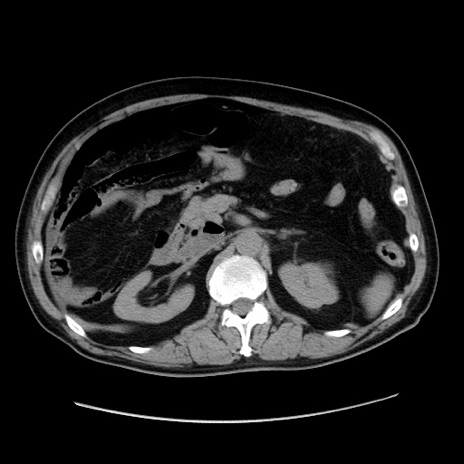

症例30(横断像)

【症例】80歳代男性

【主訴】臍周囲痛

【現病歴】約6時間前から臍下部痛が出現。次第に腹部膨隆・背部痛も生じてきたため来院。背部痛の場所は変化しない。

【身体所見】意識清明、BT 36.3℃、BP  131/87mmHg、P 87bpm、SpO2 100%(RA)、臍周囲自発痛・圧痛あり、反跳痛なし、自発痛部位に一致して板状硬あり、腹部膨隆、腸雑音減弱、CVA tenderness両側陰性。

【データ】WBC 19600、CRP 0.33